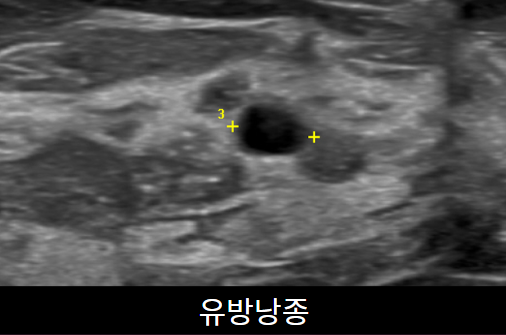

유방초음파 검사를 통해 유방낭종,염증, 종양을 진단할 수 있습니다. 유방촬영술과 같이 진행하는 것이 이 정확한 진단을 위해 필요합니다. 약 10~15분 소요됩니다.